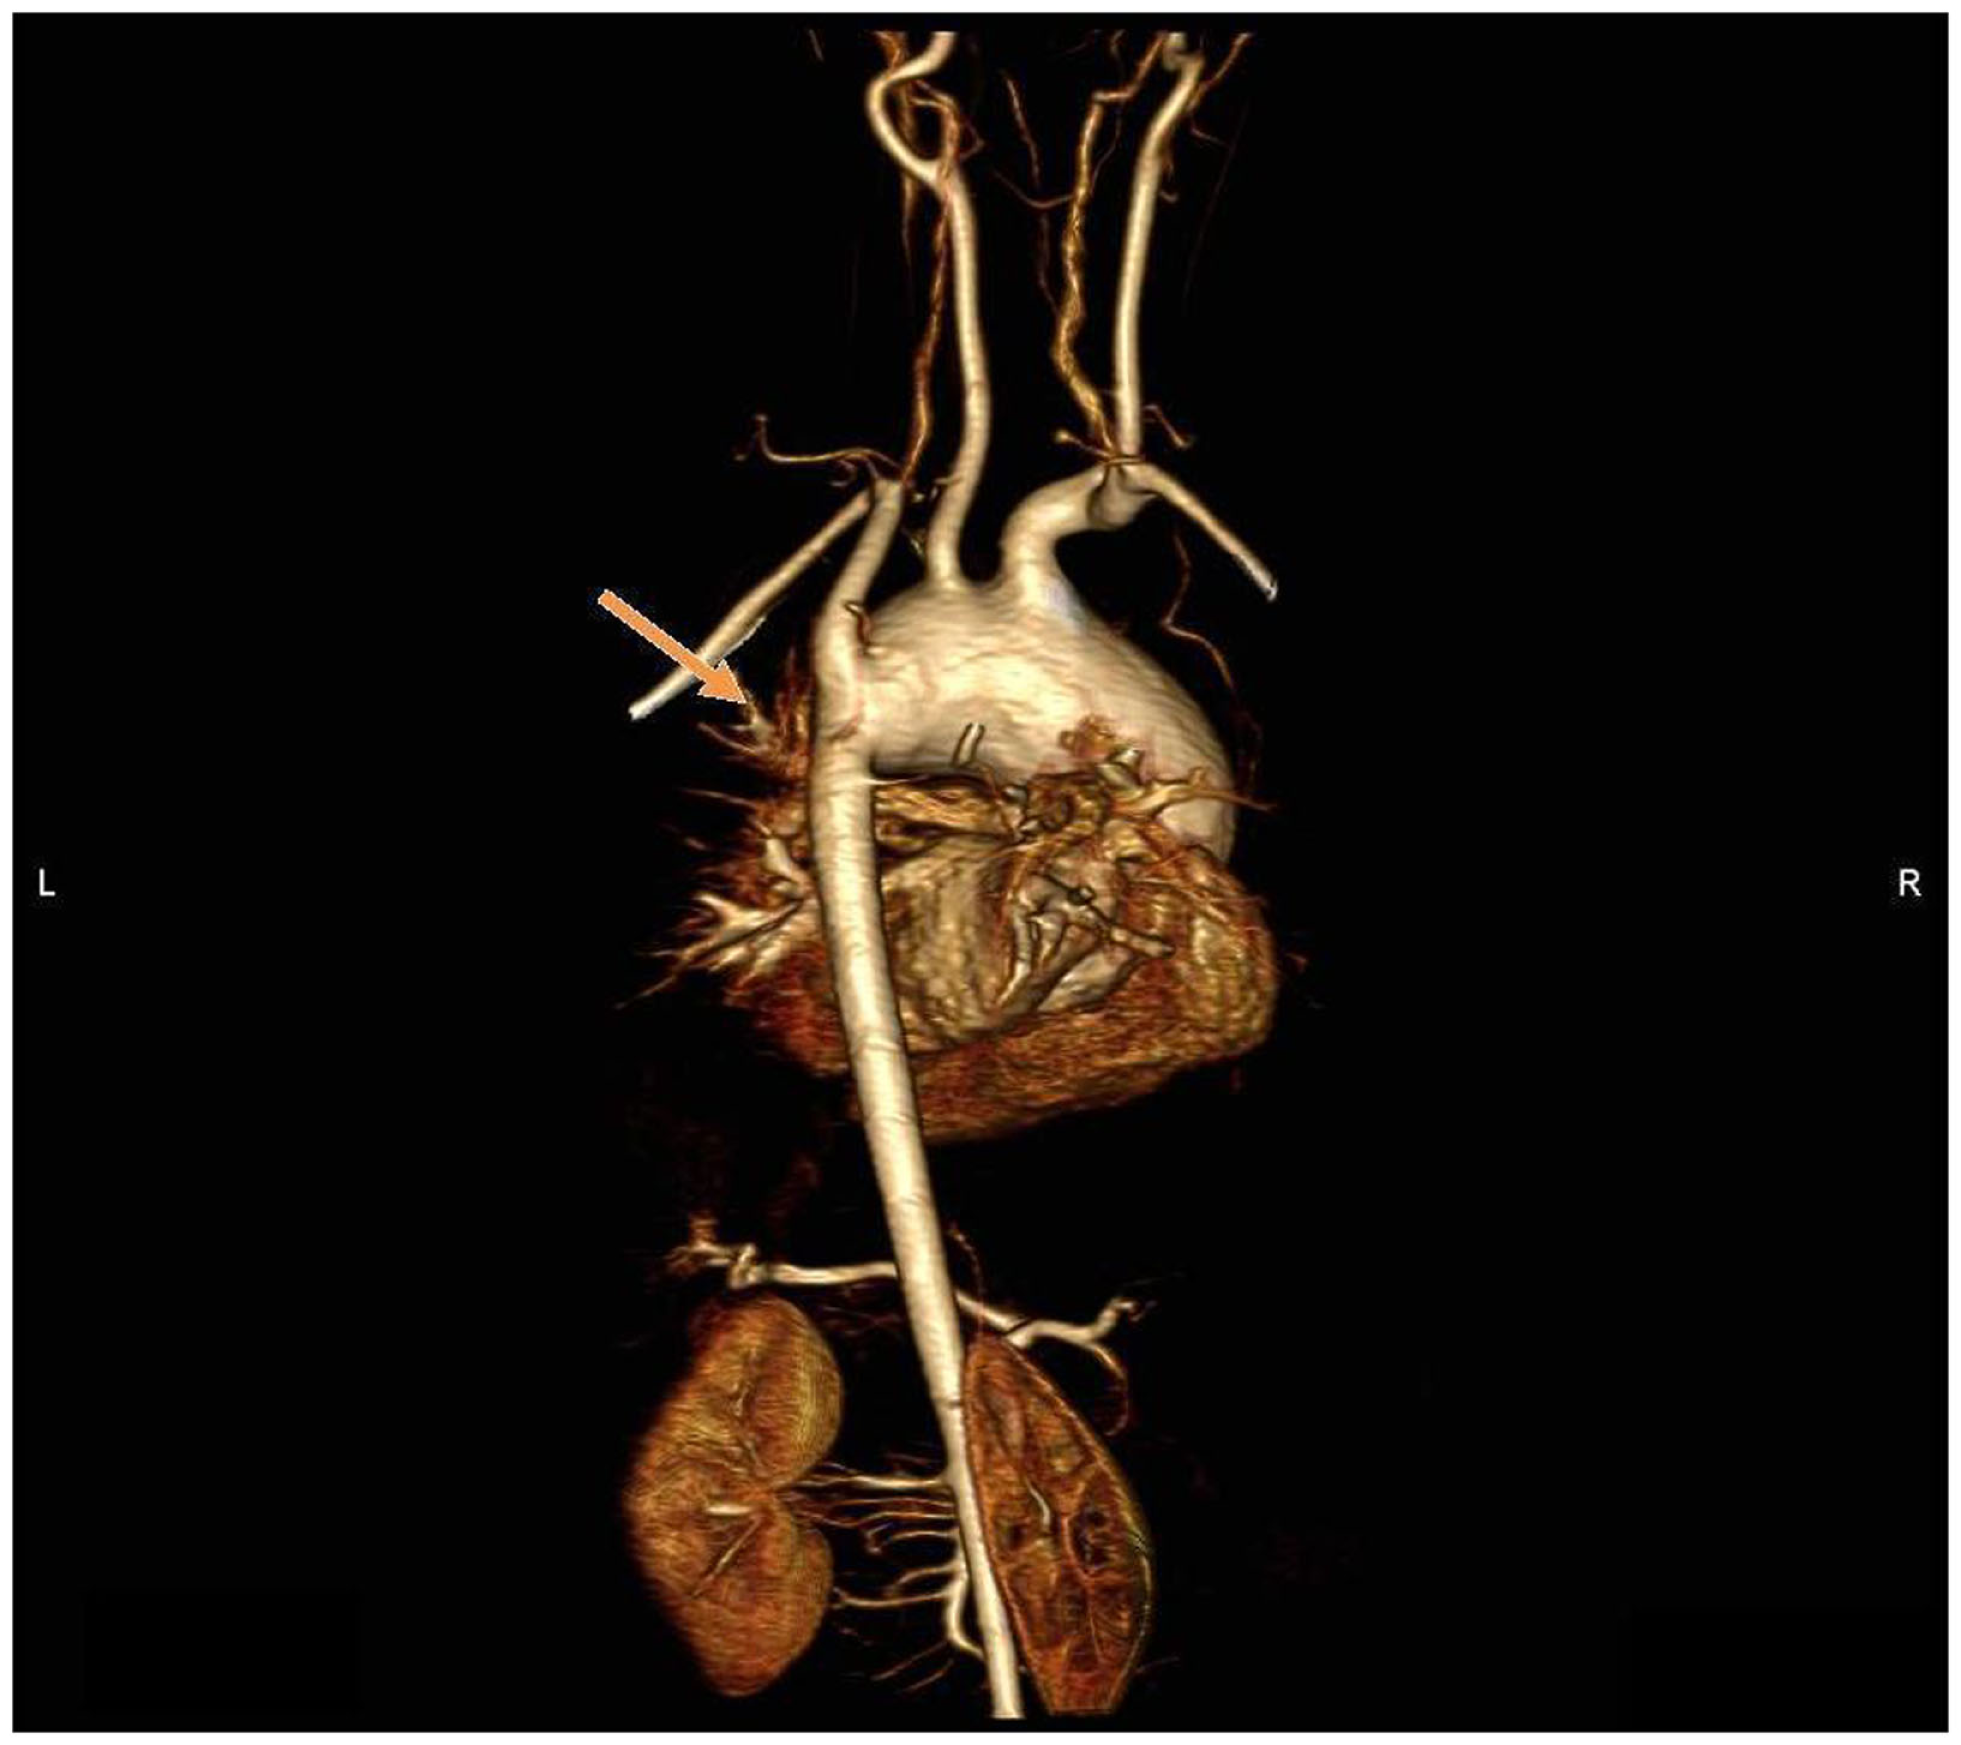

Figure 6

MR angiography, volume rendering 3D reconstruction. Posterior view of the aortic arch before surgery.